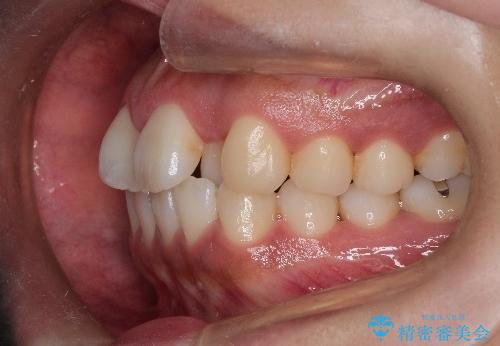

初診時の歯並びの状態としては、上下ともに全体に及ぶの中等度のがたつき(叢生)があり、全特に左上の前歯は1本だけ引っ込んでいる状態でした。

抜歯は行わず上顎の奥のスペースを利用して歯をスライドする方法の他に歯列弓の拡大やディスキング(歯と歯の間の隙間を作る処置)を行い叢生を改善しました。

歯の大きさの不揃いが原因の正中のズレは、ディスキング量を調整することで合わせました。